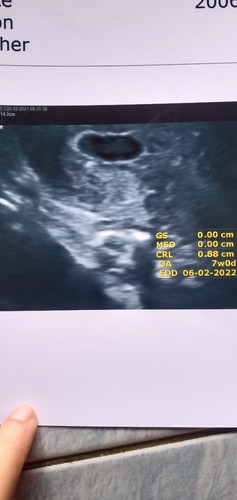

แม่ๆฝากครรภ์ครั้งแรกกันกี่วีคคะบ้านนี้ฝาก7wยังไม่เห็นหัวใจน้องเลยหมอนัดอีกทีวันที่4กรกฎาคมแอบกังวลนิดนึงค่ะเพราะยังไม่เห็นหัวใจน้องเลย😅😅😅

บ้านซาวด์ตอน6วีคเจอตัวกับถุงและรูปล่างตอน8วีคเห๋นหัวใจน้องเต้นแล้ว...แม่ใจเย็นๆนะคะรอบหน้าก็คงเจอน้องแล้ว..ยินดีด้วยค่ะแม่

เจอน้องตอน 7 week เห็นตัว เห็นหัวใจกะพริบ ได้ยินเสียงหัวใจ ไปซาวเมื่อวันที่ 18/6 นี่เองคะ #ท้อง2ค้า

วันนี้ไปพบหมอมาค่ะ เจอหัวใจน้อง7w+6 คุณแม่อย่าาเครียดน่ะค่ะ อดใจรออีกนิด